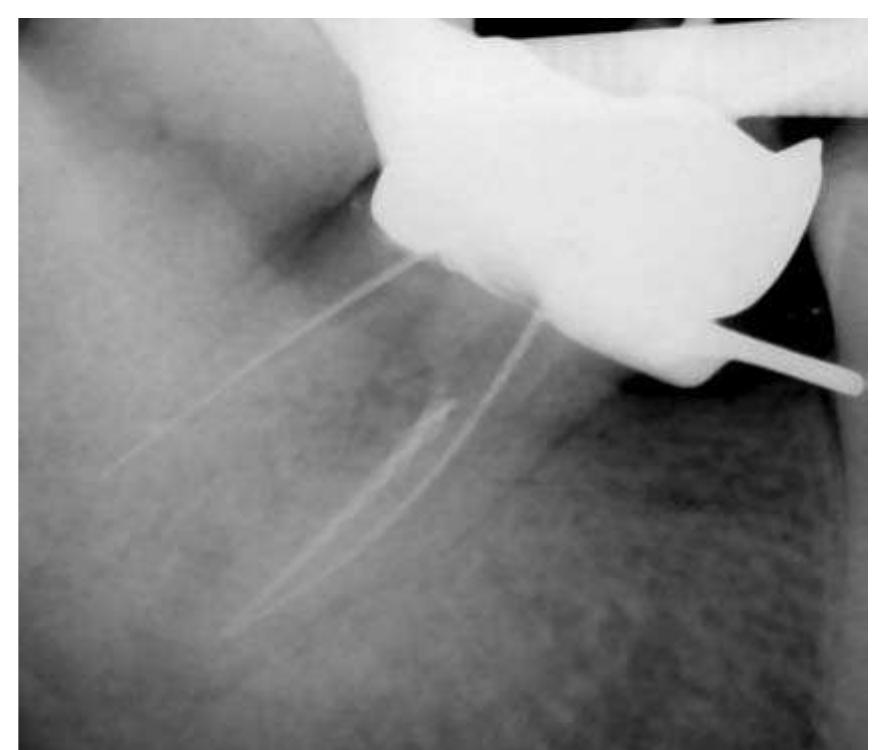

- There is little root filling material present and the root canal would undoubtedly be infected.

- An attempt at root canal treatment has been made but the root canals are extremely fine and have not been successfully negotiated.